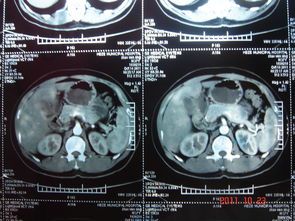

在CT掃描中,凡小于層厚的病變,其CT值受層厚內(nèi)其它組織的影響,所測(cè)出的CT值不能代表病變的真正的CT值:如在高密度組織中較小的低密度病灶,其CT值偏高;反之,在低密度組織中的較小的高密度病灶,其CT值偏低,這種現(xiàn)象稱為部分容積效應(yīng)。由掃描分辨率而決定的部分容積效應(yīng)是一個(gè)關(guān)系重大的技術(shù)因素。

改變窗寬窗位也可以呈現(xiàn)不同變化。

窗寬窗位的調(diào)整是數(shù)字圖像后處理工作中的一項(xiàng)常規(guī)內(nèi)容,又是圖像顯示技術(shù)中最重要的功能。正確選擇和運(yùn)用窗口技術(shù)是獲得優(yōu)質(zhì)圖像和提高診斷率的重要手段。